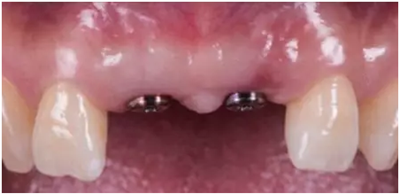

種植過渡義齒戴牙后1個(gè)月,患者希望改善義齒美觀度,并進(jìn)一步減少唇側(cè)凸度

患者試戴1個(gè)月后,發(fā)現(xiàn)牙齦塑性效果良好,過渡義齒穿齦部分不需要修改

種植過渡義齒戴牙后3個(gè)月,牙齦形態(tài)穩(wěn)定

過渡義齒制作完成及試戴

過渡義齒佩戴3個(gè)月后